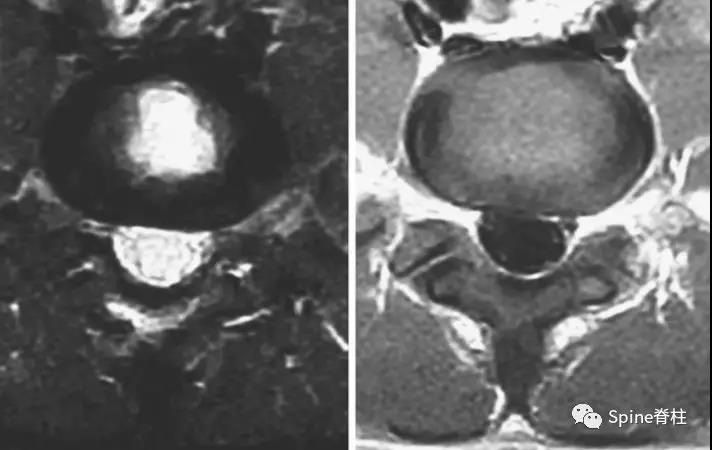

图:术后情况

症状性椎弓根裂和椎板裂的治疗与峡部裂类似,应早期诊断,早期进行保守治疗。